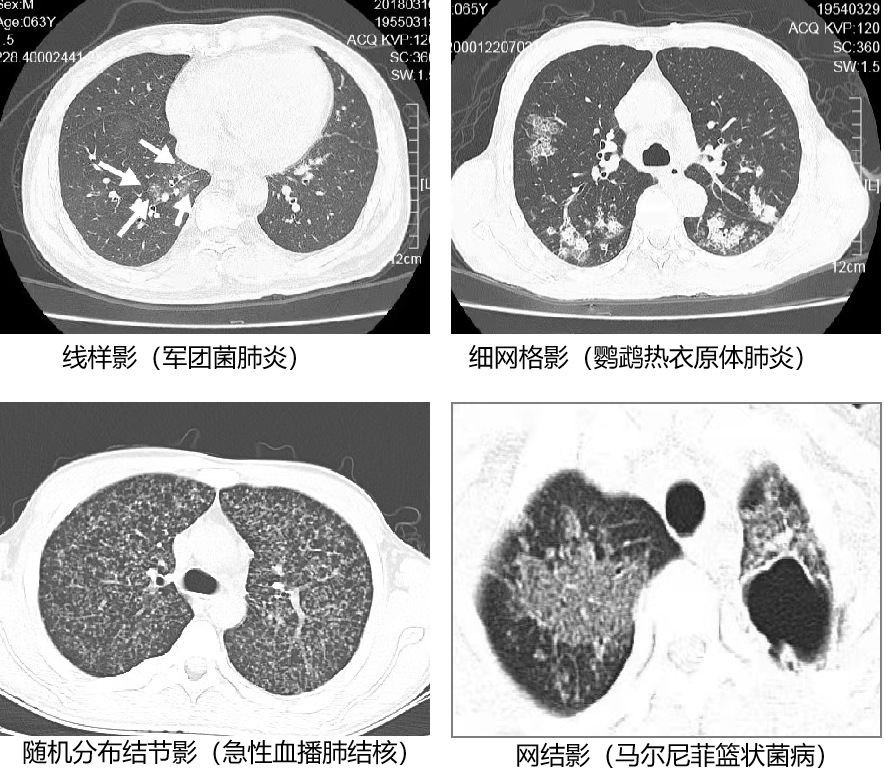

5. 间质性肺炎的 4 种形态:

2.  肺泡性肺炎的最初形态是腺泡结节;支气管肺炎的最初形态是树芽征及围绕小叶中心细支气管的结节;间质是肺内与空气不接触的部分,间质性肺炎有 4 种模式:线样影、网格影、结节影、网结影。

4.  需要特别指出的是,衣原体肺炎(包括肺炎衣原体肺炎及鹦鹉热衣原体肺炎)、立克次体肺炎、钩端螺旋体病肺型本质上是感染性血管炎,影像判断时需要注意。